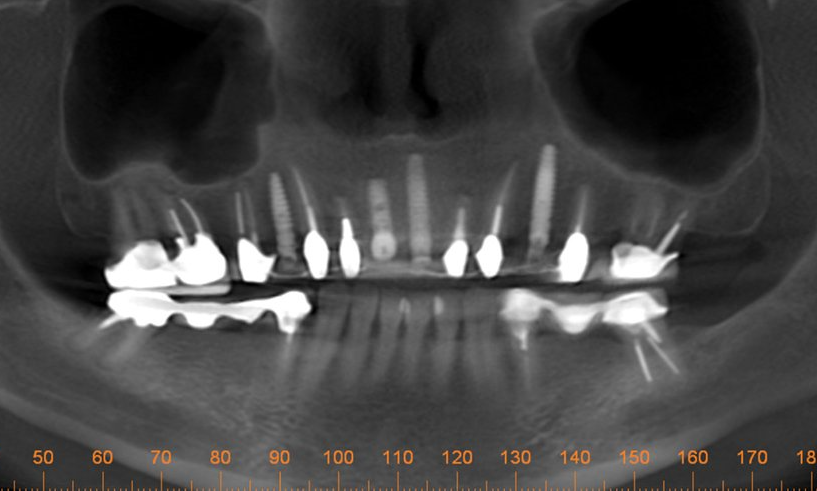

One day a 50 year-old patient and dentist friend of mine, (who already has multiple dental implants) came to my office and presented with a non-restorable fractured tooth number 8 (Figure 1). As you can see from the photograph, this looked to be a complicated extraction. As always, my treatment plan consists of proper imaging. With dental implant cases it usually involves the i-CAT. (Figure 2)

The primary challenge was to remove tooth number 8, while maintaining the soft tissue and bone intact. As I have mentioned in previous articles, I will strategically plan out the entire case before beginning any procedures. The plan was to extract tooth #8 and place an immediate implant. Since there was no root to grab on to, and lifting a flap would compromise the buccal bone, I decided to utilize a new instrument on the market called Benex® Control, an atraumatic tooth extractor by Meisinger USA. I feel one has to have state-of -the-art tools and technology at their disposal for just the right application. This case was an ideal case for the Benex® Extractor. This device works like magic for removing single roots without lifting a flap or cutting bone.

The implant osteotomy is performed slightly palatal to allow a small minimal gap between the future implant and the buccal bone. The pilot drill with the MIS implant system is used to start the osteotomy. Then the next two larger drill sizes are used to enlarge the osteotomy site further. The implant I chose was a MIS 7 implant 3.75 x 11.5 mm tapered implant with aggressive threads that finds its way by self-tapping into the osteotomy.